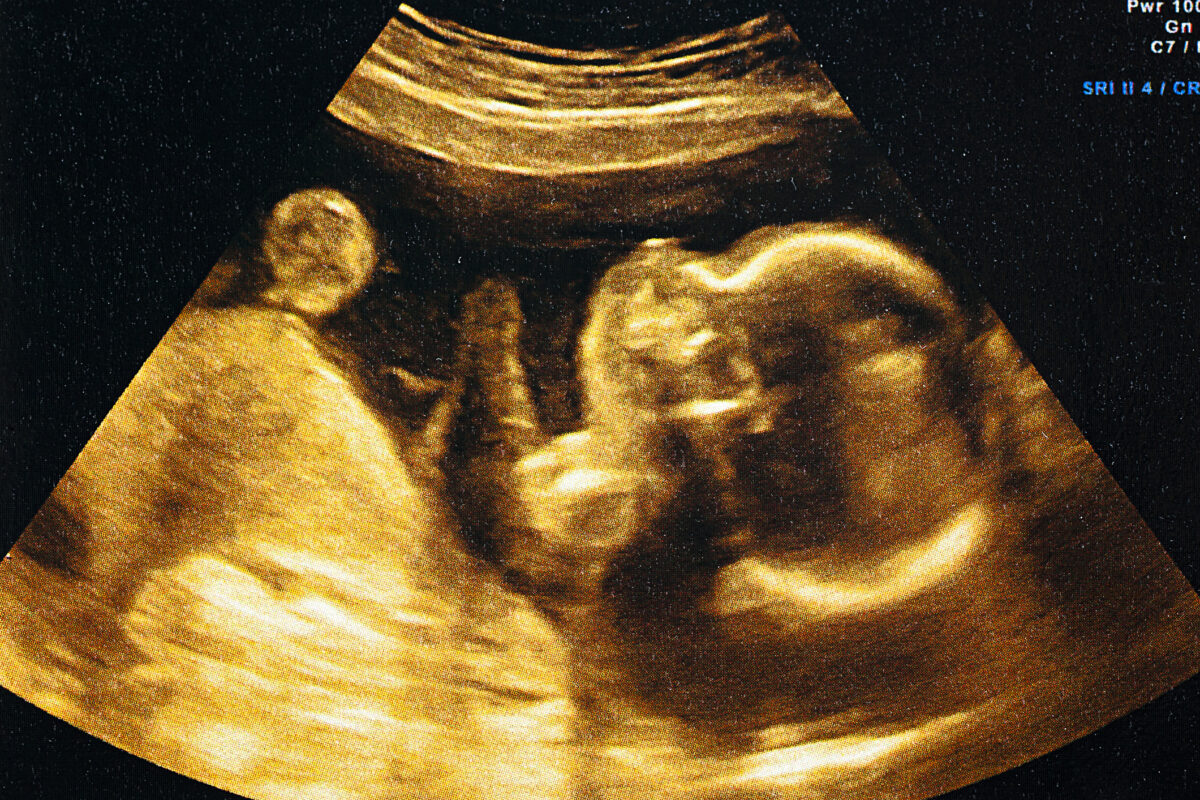

Προς το τέλος του έβδομου μήνα της εγκυμοσύνης εντοπίστηκε ο όγκος (σύνδρομο Κάσαμπακ-Μέριτ) στο έμβρυο, σε μια μαιευτική κλινική της Μιλούζ, στην ανατολική Γαλλία.

Γαλλία – Ο όγκος μεγάλωνε πολύ γρήγορα και είχε καλύψει όλη τη βάση του προσώπου του εμβρύου.